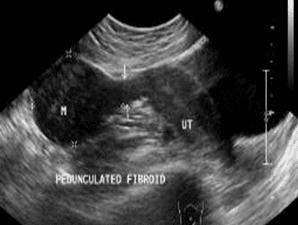

U xơ tử cung có cuống